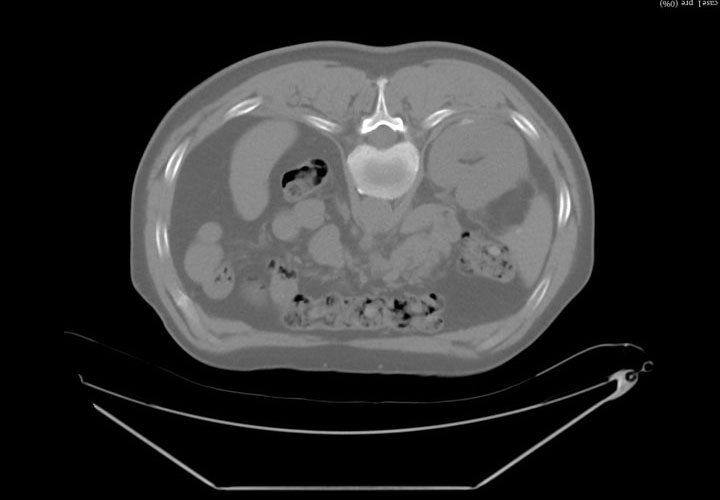

IGTFusion used to guide and confirm accurate needle placement in 3 renal lesions that were not visible on CT during the procedure.

- Registered a supine pre-procedural image to a prone procedural image